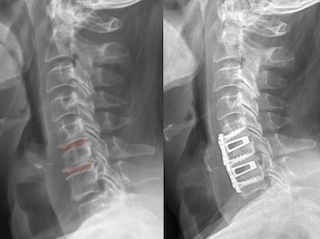

X-ray images of a human cervical spine showing a herniated disc before and after spinal surgery with hardware implanted.

ACDF surgery is typically performed through a small incision in the front of the neck.

• The surgeon carefully moves aside muscles and structures in the neck.

• The damaged disc is removed.

• Bone spurs or other structures compressing the nerves are removed.

• A spacer filled with bone graft is placed between the vertebrae.

• A small plate and screws are often used to provide stability while fusion occurs.

The procedure usually takes one to two hours, depending on the number of levels treated.